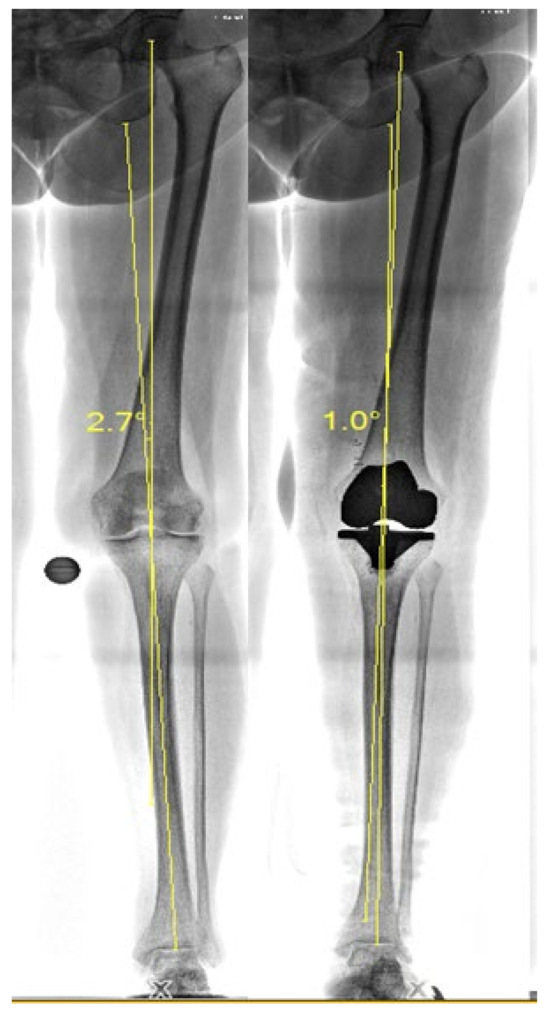

2.5. Knee Alignment